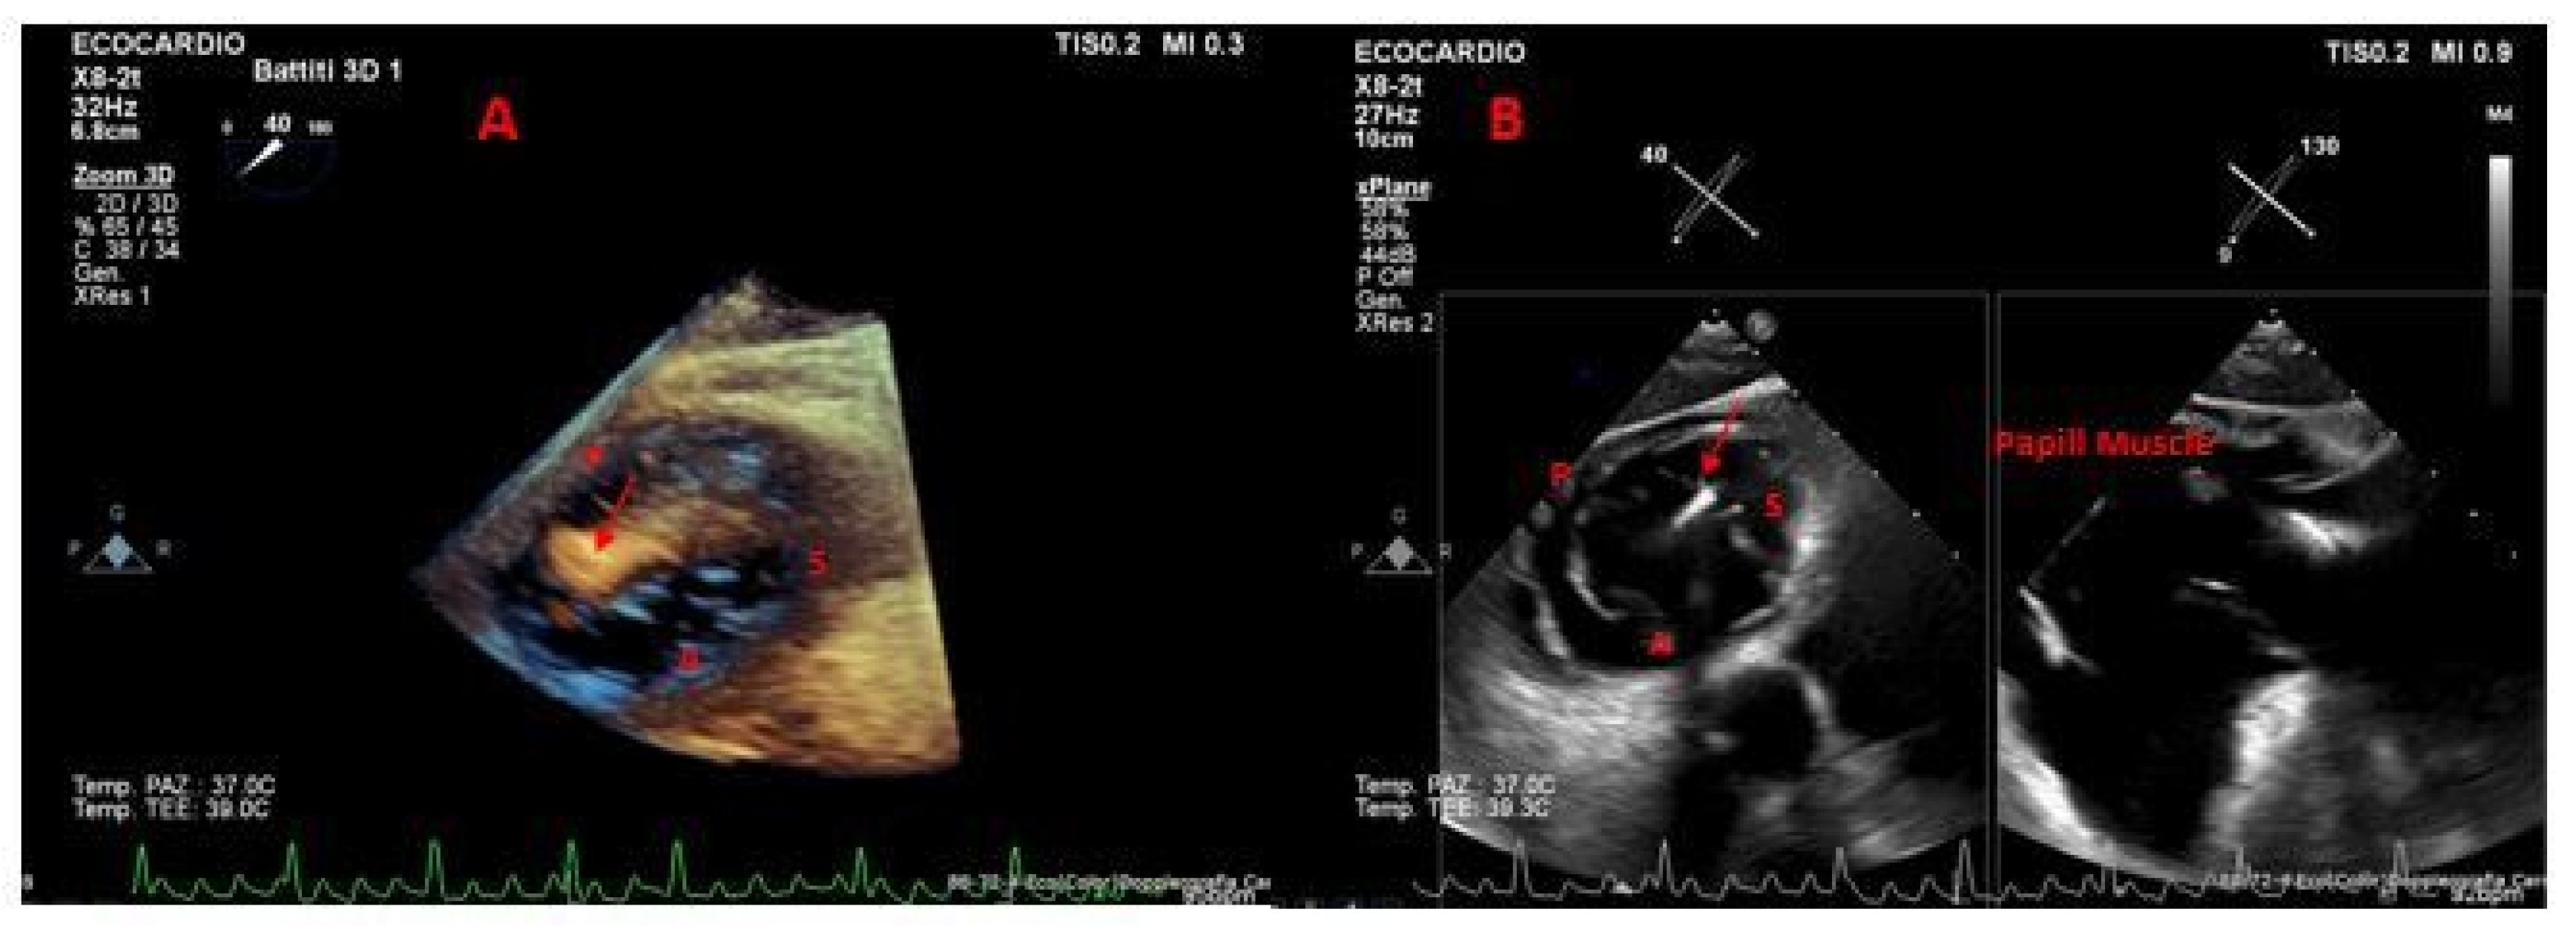

- Cammalleri, V.; Antonelli, G.; De Luca, V.M.; Piscione, M.; Carpenito, M.; Gaudio, D.; Nusca, A.; Cocco, N.; Mega, S.; Grigioni, F.; et al. 3D Transoesophageal Echocardiographic Assessment of Acute Reverse Remodelling of the Tricuspid Annulus after Transcatheter Edge-to-Edge Repair. Eur. Heart J. Cardiovasc. Imaging 2025, 26, 316–324. [Google Scholar] [CrossRef] [PubMed]